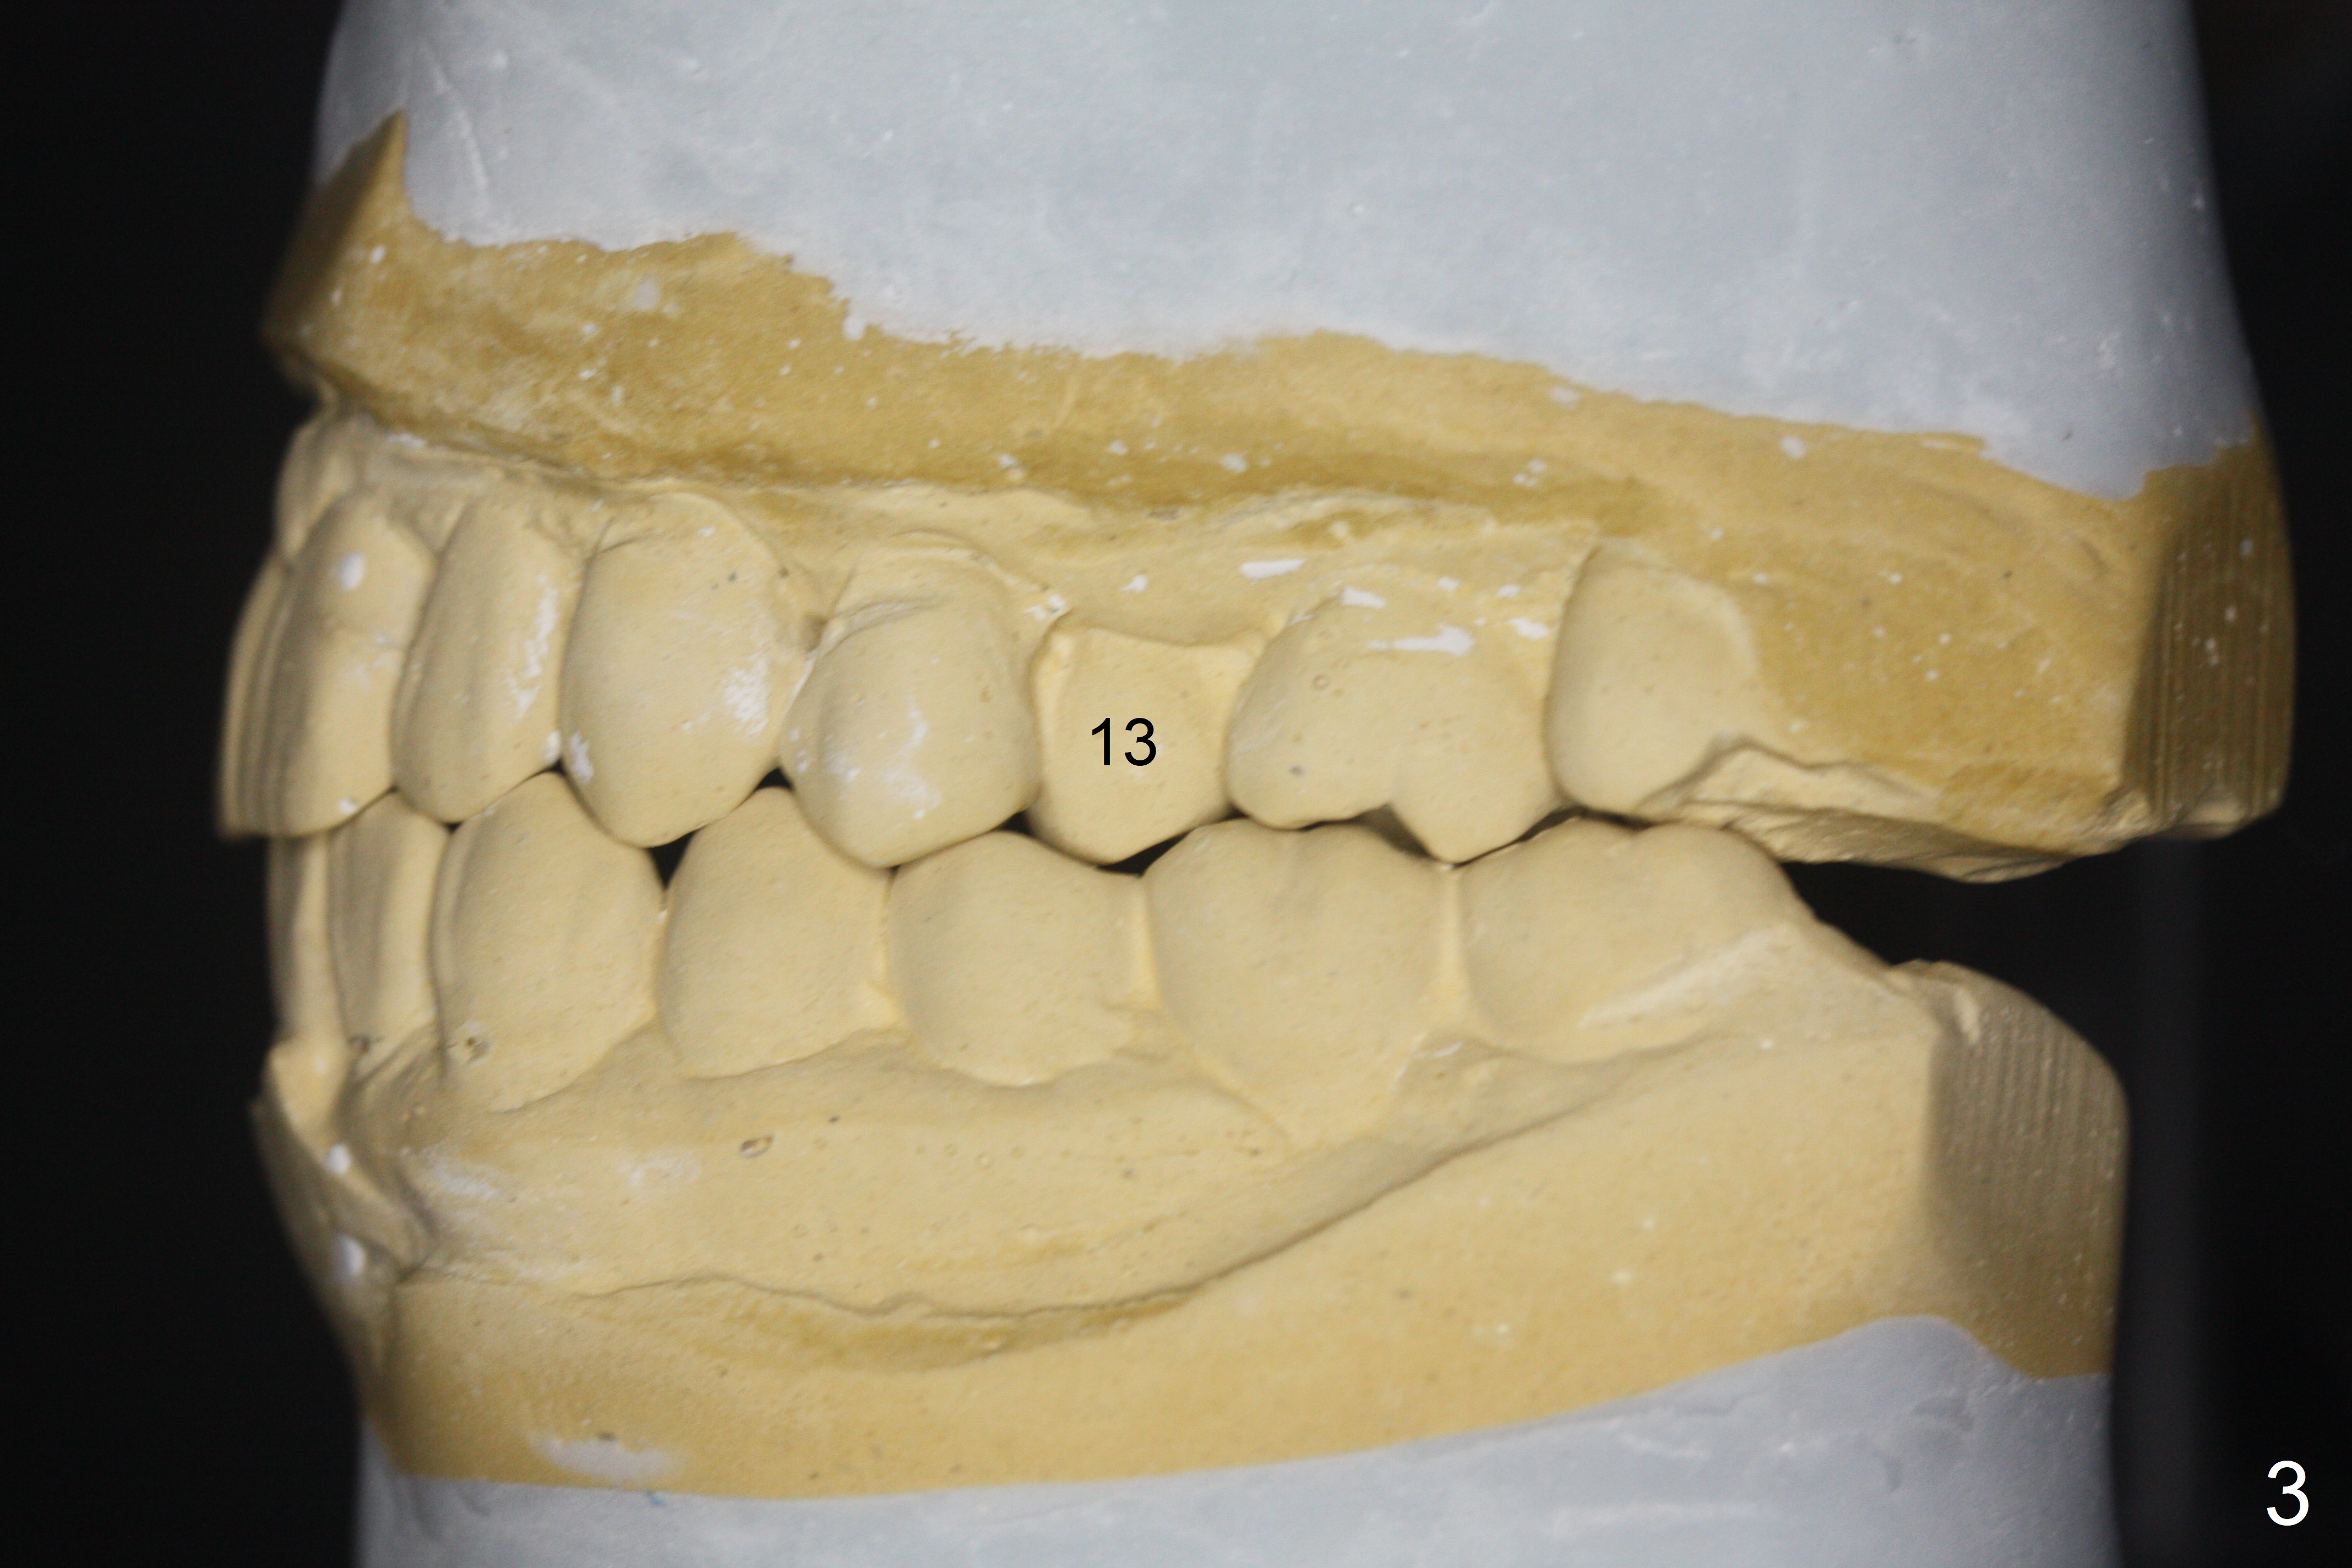

A 64-year-old man has discomfort with the lower left bridge and a loose tooth on the left (Fig.1). It appears that 4 implants are to be placed at #18,19,30 and 31. Since the tooth #4 and 13 are palatalized (Fig.2-4), the teeth #2 and 3 are mesialized (Fig.2 arrow). Besides, the ridge at #30 must be atrophic due to long termed edentulism. A small-diameter implant will be placed at #30 with premolar width (Fig.6-13), while the implant at #31 will be placed distal (arrow, as compared to Fig.2). To establish harmonious occlusion at provisional and final stages, the palatal slope of the mesiopalatal cusp of the tooth #2 will be adjusted (Fig.10).